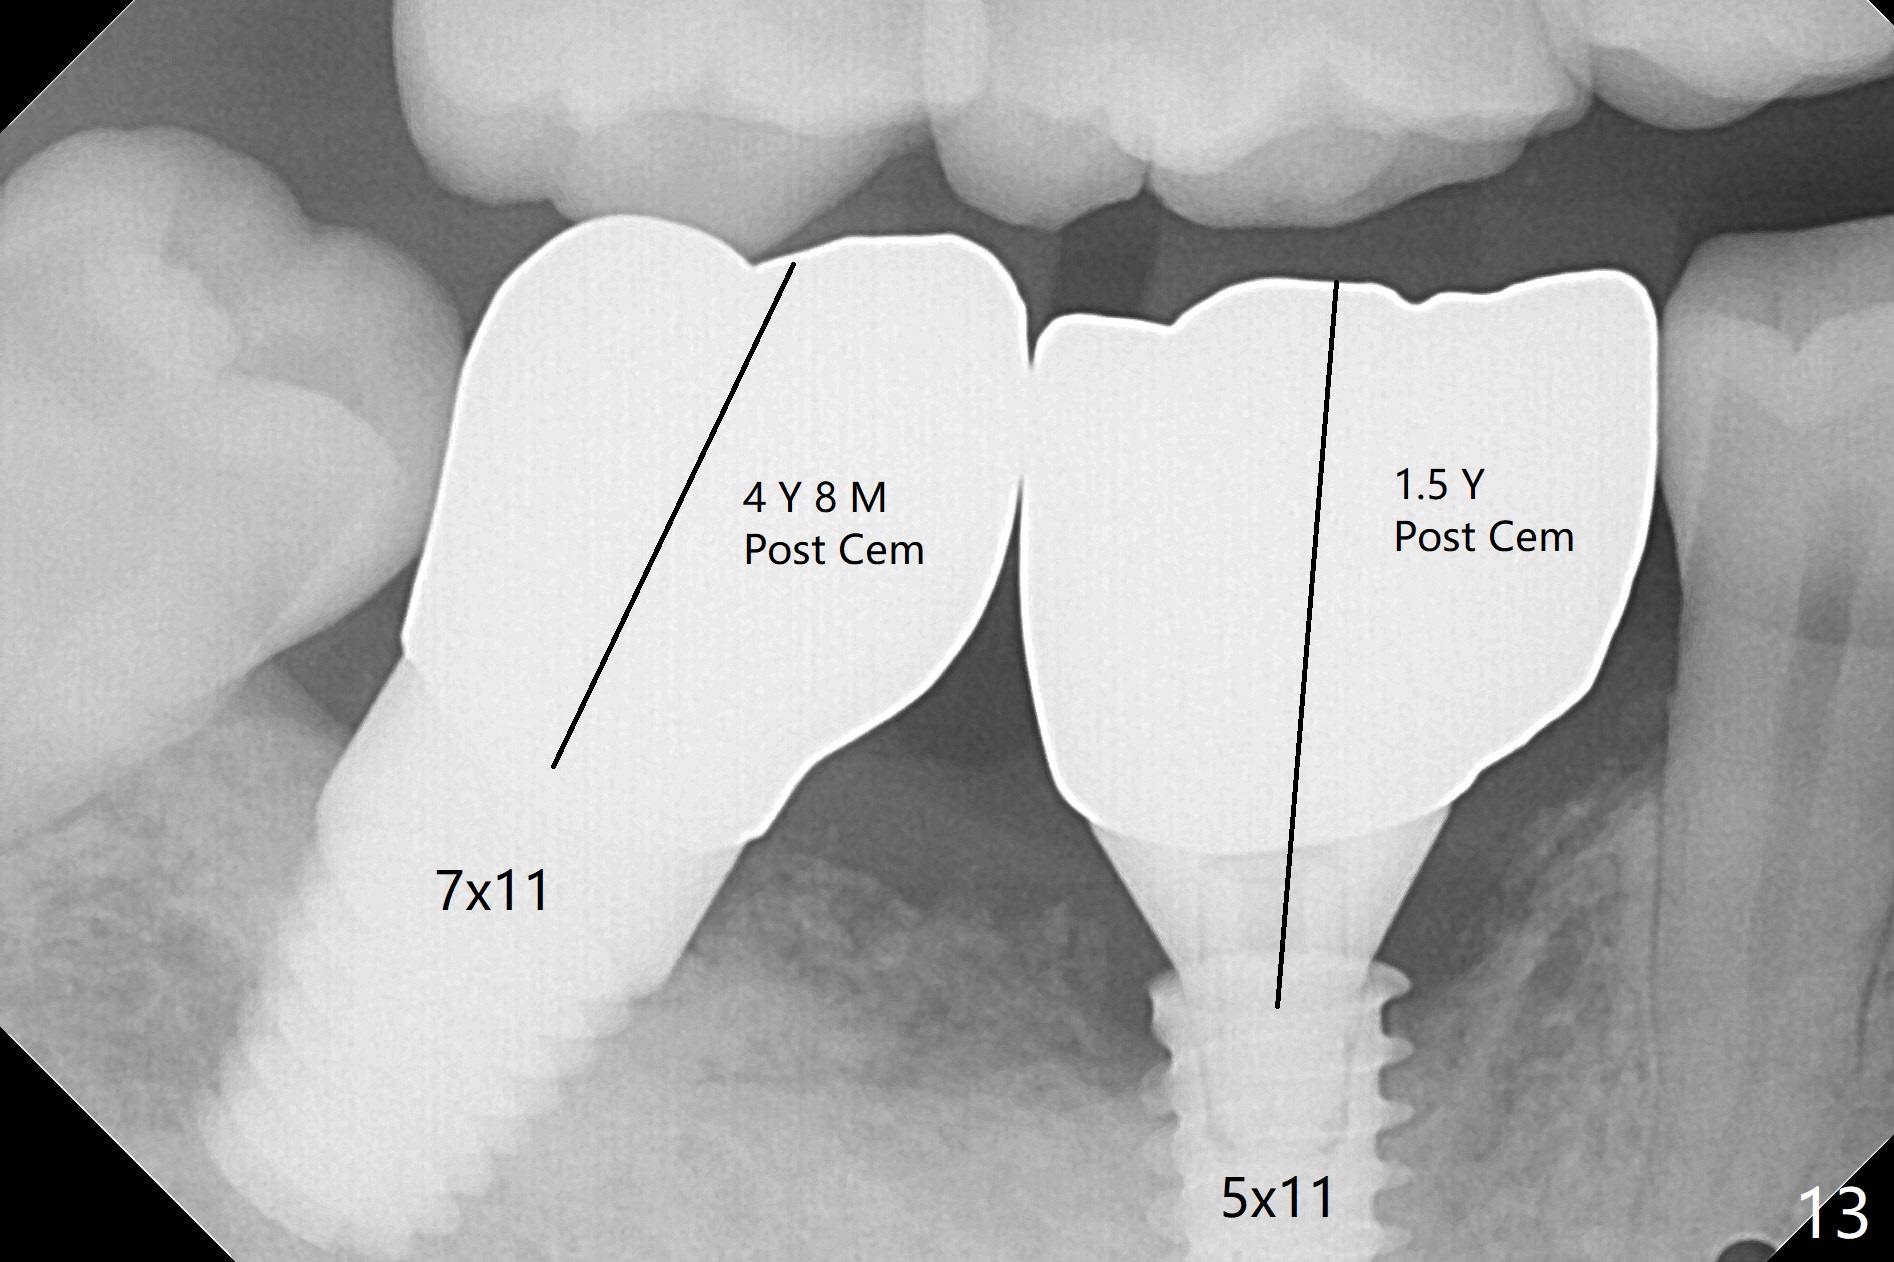

Extraction shows the large distal socket (Fig.1 D) and the thin and low septum (*) of the tooth #30. After Magic Split test confirms hard bone, osteotomy is initiated with 1.6 mm pilot drill with 11 mm stopper (Fig.2); there is 2.7 mm distance to the Inferior Alveolar Canal. Following Marking Bur, a 4.8 mm Magic Drill is used to finish the osteotomy with difficulty because of hard bone and ineffective local anesthesia due to infection. A 5x9 mm "dummy" implant is placed to determine the placement level relative to the distal crest (Fig.3 *). After removal of the dummy implant, an authentic one with the same dimension is placed with packing abundant allograft (.5-1.5 mm) and Osteogen (Fig.4 *); it appears that 4 to 5 threads (fins) of the implant (arrowheads) are engaged to the native bone for primary stability (>40 Ncm). Later more bone graft is placed distally (Fig.5 arrow). With the short implant placed not so deep, there is 6-7 mm clearance from the underlying canal (Fig.6). The patient is doing well 7 days postop (Fig.7). He feels that the provisional is too bulky buccally for the first 2 days postop. The buccal margin will be trimmed in another 2 weeks (dashed line). The patient in fact masticates on the right side postop. By the time he returns for provisional revision 1 months 10 days postop, he has mild pain. There is food entrapment. The provisional and the abutment are slightly loose, whereas the implant is stable with healing socket (Fig.8). A healing abutment is placed. The implant appears unstable nearly 5.5 months postop. The gap between the bone and implant seems to be large (Fig.9). The implant should have been larger and longer for fast healing. A healing screw is used instead. The site heals 10 months postop with an increase in bone density around the implant (Fig.10.) Prior to cementation of the final crown, the abutment is minimally exposed (Fig.11 (6.5x5.7(3) mm)). In fact the abutment screw becomes loose 2 months post cementation (1 year postop); it appears that crown/implant ratio is unfavorable (Fig.12). The implant is slightly placed mesially (cantilever). The patient cannot chew on the left. The tooth #19 is periodontally affected and the tooth #18 is missing. When bone loss is severe, the implant should be as large as possible and preferably tissue-level. The abutment screw is re-loosening 1.5 years post cementation (4 months post #19 socket preservation, Fig.13). The crown/implant ratio at #31 is more favorable than that at #30 (compare black lines). The crown at #31 has large contact area with the tissue-level implant (external), whereas the contact between the abutment and the bone-level implant is much less (internal). To prevent the abutment screw re-loosening (turning) in function, a screw driver (Fig.14 D) will be buried inside the crown/abutment after the screw is retightened. Make sure that the driver is in the middle of the access hole. Section the driver in situ obliquely (Fig.15); flat sectioning allows the driver to turn with the abutment screw in function. After insertion of plumber tape around the sectioned screw driver, use composite to fix the driver in place and seal the access hole (Fig.16). Occlusal check suggests weak link between the abutment and bone-level implant at #30.